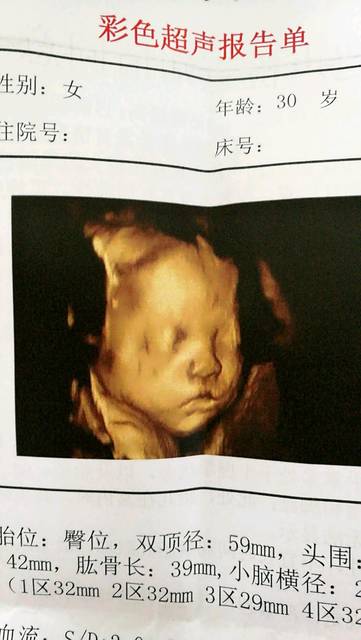

四维结果,右侧双肾孟未见明显分离_24周人民医

720x960 - 579KB - JPEG